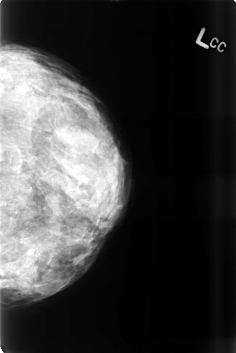

B_3469_1.LEFT_CC

LEFT_CC LINES 4584 PIXELS_PER_LINE 3056 BITS_PER_PIXEL 12 RESOLUTION 50 NON_OVERLAY